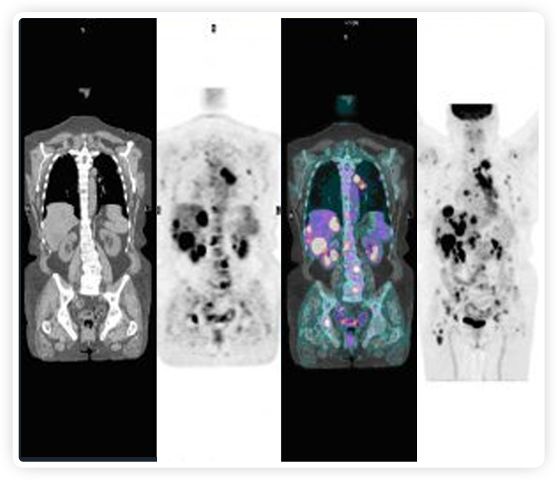

PET+放療共同治療

RefleXion將PET成像與立體定向放射治療相結合。在注射示蹤劑后,RefleXion的技術基于示蹤劑信號實時地在一個或多個目標上引導治療性X射線。使用這種專有方法,RefleXion的平臺有可能比現(xiàn)有系統(tǒng)向癌癥病變提供更高劑量的輻射,并改善周圍健康組織的保護。

為了避免PET長圖像采集時間,RefleXion開發(fā)了一項專利技術使用重合的PET光子對來指導放射治療束,因為實時檢測發(fā)射的光子,為生物指導提供了一種時間有效的方法。